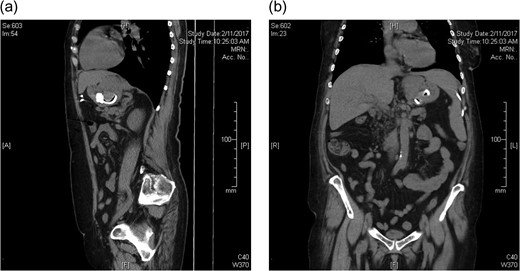

A 65-year-old female presented with a 6-week history of vomiting. This had progressed to complete intolerance of all solid and liquid oral intake, except for small sips of water. The patient also described epigastric discomfort followed by a band-like pain around the circumference of her thorax, at the level of the epigastrium. Her LAGB had been performed at another institution 19 years prior. There was subsequent tightening of the gastric band three years following initial placement. Due to geographical relocation of the patient, there was no formal follow-up. The patient reported acceptable weight loss and maintenance, with no adverse symptoms. She had an unremarkable abdominal examination. Computed tomography imaging identified oral contrast pooled above the level of the laparoscopic band, at a much lower level in the stomach than expected. The small and large bowel were collapsed and almost gasless, suggesting band slippage and absolute obstruction (Fig. 1a and b). Exploratory laparoscopy and removal of the gastric band was performed on the following day.

CT abdomen prior to laparoscopic gastric band removal (a) sagittal and (b) coronal.